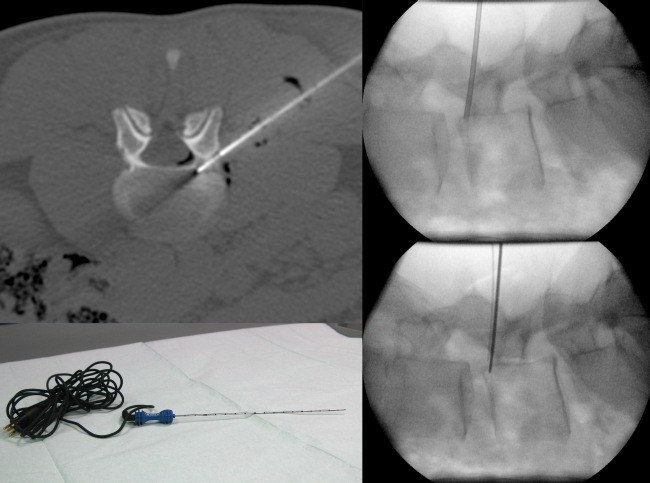

Bei der perkutanen Radiofrequenzablation wird unter Narkose und CT-Kontrolle der für die Schmerzen ursächliche Osteoidosteom-Nidus in koaxialer Technik von perkutan mittels einer Knochenpunktions-Kanüle sondiert und im Anschluss eine Thermosonde (Abb. 1 a-c, 2 a-c) mit ihrer aktiven Spitze durch diese koaxiale Kanüle vorgeschoben und zentral im Osteoidosteom platziert. Durch Zurückziehen der Koaxialnadel wird die aktive Spitze der Thermosonde freigegeben, um eine vollsta¨ndige thermische Destruktion des Nidus zu ermo¨glichen. Bei dieser Methode wird in den Nidus ein hochfrequenter elektrischer Wechselstrom (375–480 kHz) u¨ber einen nicht isolierten Anteil der Thermosonde verabreicht, wobei es im Gewebe zur Ionenagitation kommt, welche in manchen Fällen durch die vorherige Gabe von wenigen Millilitern einer hypertonen (20%igen) NaCl-Lösung über die koaxiale Kanüle verbessert werden kann. Da die Ionen den Richtungsänderungen des Wechselstroms folgen resultiert eine Reibungshitze, die zur Koagulation des Nidus führt, da nur das die Elektrode umgebende Gewebe und nicht die Elektrode selber erhitzt wird. Diese Thermokoagulation wird mit Hochfrequenz-Leistungen von zuerst 2 Watt für eine Minute unter Erhöhungen der Hochfrequenz um jeweils ein Watt pro Minute mit den jeweiligen Impedanz-Anstiegen nach einer Zeit von durchschnittlich 5 bis maximal 15 Minuten bei ca. 90° C bis zum sog. „Roll-Off“ durchgeführt:

Bildlegenden Abb. 2 a-c MR-tomographische und CT-morphologische Darstellung eines 5 x 4 mm großen Osteoidosteom (Pfeile) mit einem zentral verkalkten 1,5 mm großen Nidus kranial im linken Pediculus arcus vertebrae von LWK 4 bei einem jungen Patienten mit nächtlichen starken Schmerzen (VAS 9) seit fünf Monaten, welche bisher mit einer NSAR-Dauertherapie behandelt wurden. In der MRT zeigte die Läsion eine ca. 30 x 25 mm große umgebende knochenmarködem-äquivalente Osteitis (Sterne), welche mit einem CT-morphologisch erkennbaren mattglasartigen Sklerosesaum korrelierte. Durchführung der Radiofrequenzablation in der CT mit simultaner Fluoroskopie mittes eines C-Bogens am CT in Vollnarkose in Bauchlage. Nach Darstellung des Osteoidosteoms durch eine hoch aufgelöste Mehrzeilenspiral-CT mit koronaren und sagittalen Rekonstruktionen wurde unter sterilen Bedingungen und unter zusätzlicher lokaler Anästhesie zuerst unter Fluoroskopie- und CT-Monitoring mit einer 2,4 mm durchmessenden Ostycut-Biopsiekanüle ein Knochenkanal von links dorsolateral zum Nidus gebohrt und eine Gewebeprobe aus der Nachbarschaft des Nidus entnommen. Im Anschluss wurde eine Hochfrequenz-Ablation bzw. Radiofrequenzablation des Osteoidosteoms durchgeführt, wobei nach Positionierung einer koaxialen CoAccess TM-Kanüle am Nidus zunächst 2 ml 20%ige Kochsalzlösung über diese Hohlnadel an den Nidus zum Zwecke einer Bereitstellung eines höheren Ionenangebotes appliziert wurde und dann eine sog. Soloist TM (Boston Scientific) Single-Needle-Radiofrequenz-Elektrode (Abbildung) unter CT-Monitoring und Fluoroskopie-Monitoring bis an den Nidus herangeführt wurde. Über eine parallel in der Nachbarschaft des Nidus im Neuroforamen platzierte 0,9 mm durchmessende Shiba-Kanüle erfolgten Luftinjektionen zum Erreichen eines protektiven Luftpolsters zur Schonung der Nervenwurzel L3 links einerseits und der Rückenmarkhäute andererseits. Erst danach wurde mit Hochfrequenz-Leistungen von zuerst 2 Watt für eine Minute unter Erhöhungen der Hochfrequenz um jeweils ein Watt pro Minute mit Impedanz-Anstiegen nach einer Zeit von 10 Minuten der sog. „Roll-Off“ erreicht. Nach Umpositionierung der Elektrodenspitze um 3 mm und nach Erreichen eines zweiten „Roll-Off“ wurde die koaxial einliegende Elektrode entfernt und über die verbliebene CoAccess TM-Kanüle eine zusätzliche sog. „perkutane Alkoholablation“ (Percutaneous Ethanol Injection Therapy PEIT) mit 1,5 ml eines 95%igen Alkohols angeschlossen. Nach Entfernung der Kanüle und nach Anlage eines sterilen Pflasterverbandes konnte der Patient in der Obhut der Anästhesie in den Aufwachraum entlassen werden. Der Patient war nach der Radiofrequenzablation beschwerdefrei.